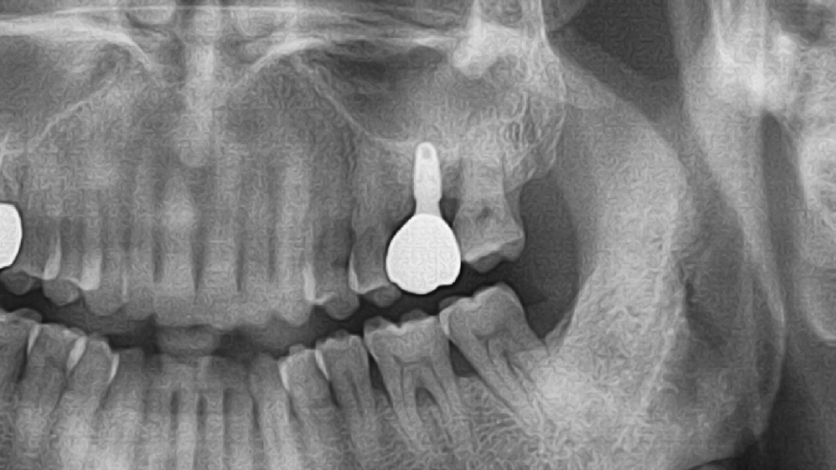

변연골 소실 최소화

- 평균 관촬 기간: 13.4 months

- 평균 변연골 소실량 : 0.027± 0.0138 mm (총 144개 임플란트)

INNO Submerged

INNO 임플란트 144개 평균 변연골 소실

0.027 ± 0.0138 mm

Other Implant

1년 평균 변연골 소실

0.21 ~ 0.99 mm

Atieh et al.(2010)의 검토에 따르면 1년 추적 관찰

기간 동안 플랫폼 전환 임플란트 주변의 평균

변연골 소실은 0.021~0.99mm였습니다.

Clinical Cases

Video